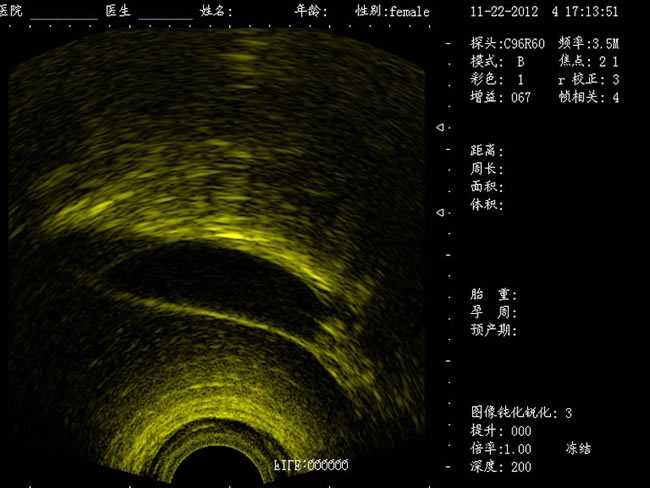

DW-460

功能特點:

婦產科手術監視儀-可視人流機掃描角度:

a) 6.5MHz腔內探頭:152º可視可調;

b) 3.5MHz凸陣探頭:60º可視可調;

TGC 調節:總增益、8 段TGC 調節器。

圖像放大:實時放大(16 級可調),局部放大(≥2 倍)。

圖像調節:黑白、左右、上下、亮度、對比度、焦點數、焦點間距、焦點位置、動態范圍、掃描角度、掃描線密度、聲功率、幀相關、M 速度。

圖像處理:圖像平滑/銳化、組織諧波、伽瑪校正、直方圖。

注釋功能:日期,時鐘,姓名,病歷號,性別,年齡,醫生、醫院、全屏幕字符編輯。

體位標記:≥30 種。